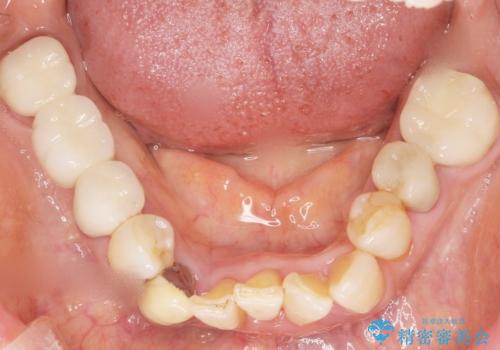

親知らずの移植 4年半経過症例 70代女性

- 親知らずの移植治療から4年半経過した患者様です。

移植した親知らずは全く問題ないそうで、「まるで自分の歯のようです。本当にすごい技術ですね。」とおっしゃって下さいました。

歯肉の腫脹や退縮、動揺も認められませんでした。

4年半前に行った自家歯牙移植に大変ご満足頂き、ご家族も紹介して下さいました。

自家歯牙移植は40歳以上の場合、若年者に比べ成功率が低くなるとの報告もありますが、状態によっては移植が可能な場合もあります。